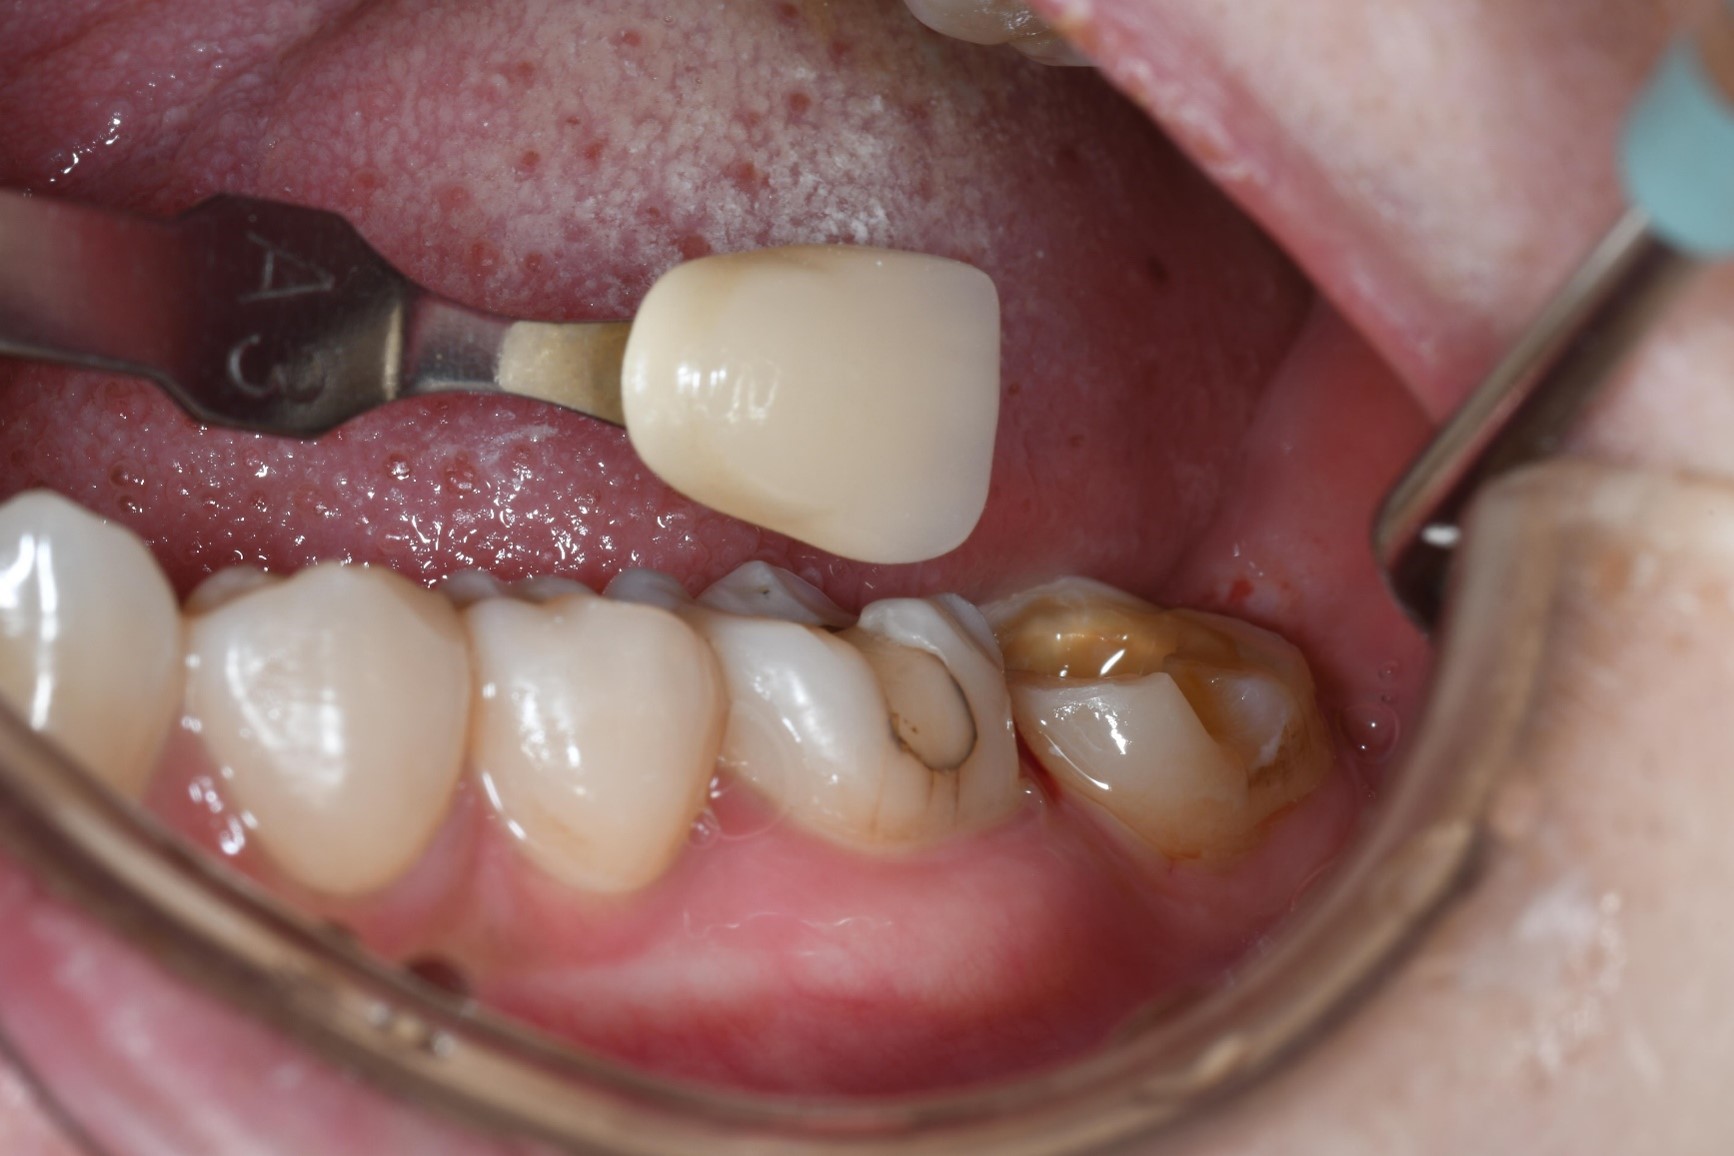

治療前,牙齒蛀牙至牙髓

牙髓受侵犯

照相比色

陶瓷冠塊體